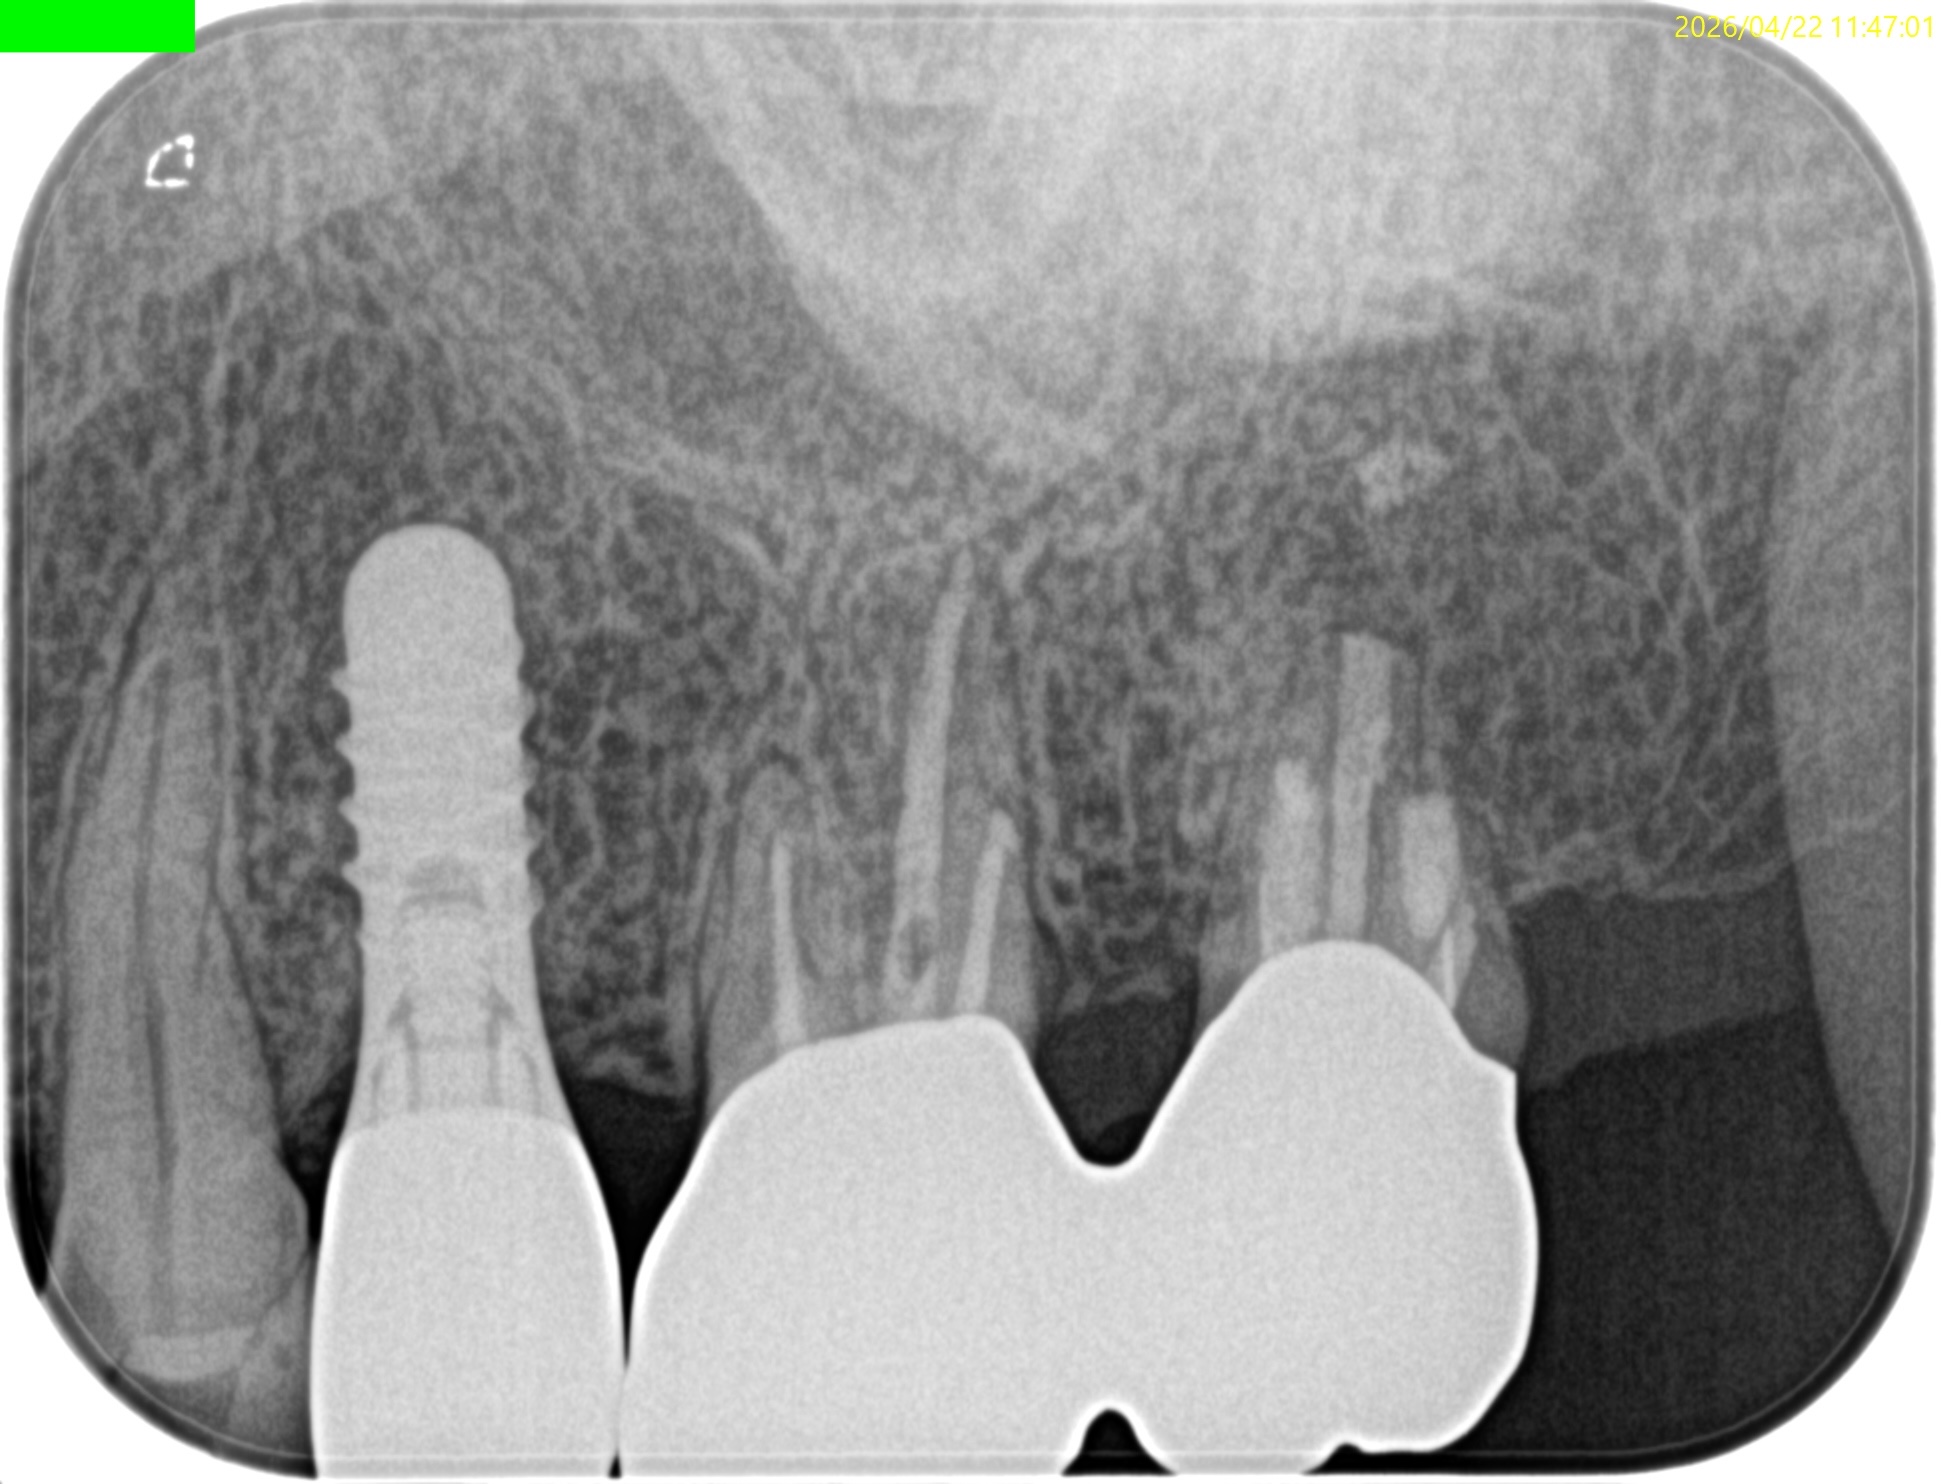

#15 Intentional Replantation 1yr recall(2026.4.22)

PA, CBCTを撮影した。

DBの破折ファイルは除去できていないが病変は消失している。